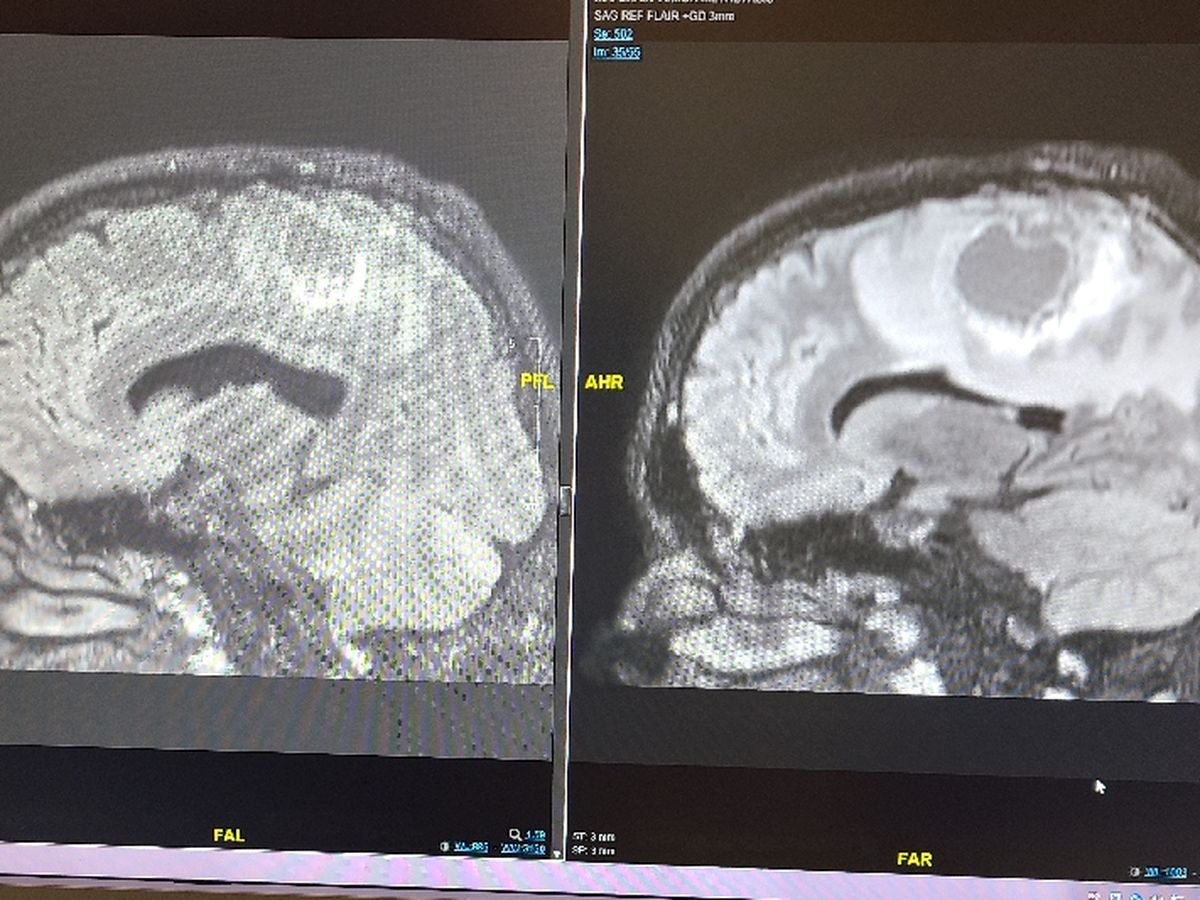

Ethan was diagnosed with an aggressive form of glioblastoma stage 4 brain cancer in June of 2020 he is done really well over the past year and a 1/2 with all his MRI scans being clear until his scan on October 7th 2021 when there was something alarming on his scan He was referred back to his neurosurgeon at Harborview where we are awaiting an appointment To find out the next steps towards his next surgery. This fund will help cover my food gas and parking while he is in the hospital and anything not covered by insurance and to help with bills at home while I'm off work for his healing and treatments.